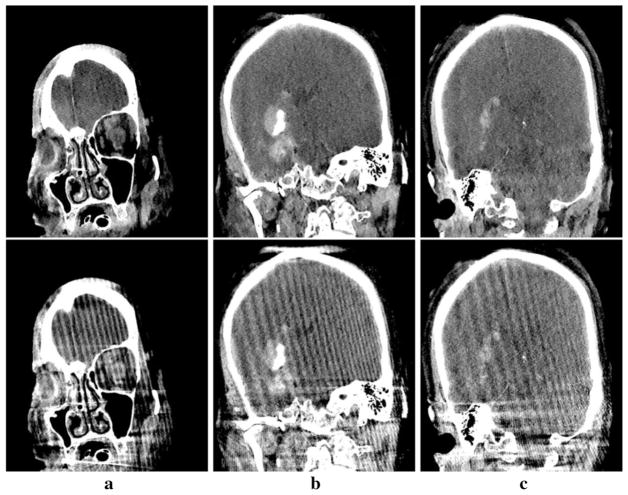

Fig. 11.

Reconstructed (row 1) and reference (row 2) images of the patient subject within sagittal slices specified by y =− 62.9 mm (a), − 2.2 mm (b), and 20.4 mm (c), respectively. Display window: [− 150, 200] HU

Fig. 12.

Reconstructed (row 1) and reference (row 2) images of the patient subject within coronal slices specified by x = 5.6 mm (a), − 2.2 mm (b), and − 46.2 mm (c), respectively. Display window: [− 150, 200] HU

For this study, we display in Figs. 10, 11 and 12 images within three transverse, coronal, and sagittal slices of the patient reconstructed, with a narrow display window for revealing details of both low-contrast structures and artifacts. Again, the images are convergent solutions to the optimization program in Eq. (1) obtained with about 900 iterations in the sense the practical convergence conditions in Eq. (14) are satisfied. The streak artifacts observed in the reference images, caused by the high-contrast interventional devices placed outside of the FOV, are significantly reduced in CP reconstructions. Moreover, the low-contrast intracranial structures in the CP reconstructions, such as hemorrhage and ventricle indicated by the arrow and the arrowhead in bottom panel of Fig. 10a, can be more discernible than those in the clinical FDK reconstruction. Conspicuous streak artifacts in the images obtained with the FDK algorithm are visually distracting and possibly obscure information of clinical significance; whereas the CP reconstructions suppress the artifacts.